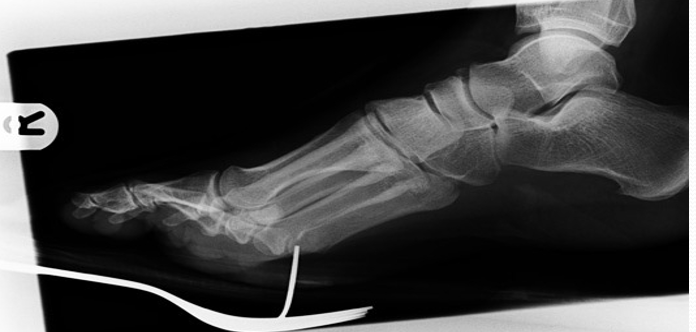

X线表现与测量

足的x线测量对于进一步了解拇外翻的病理及设计手术方案是非常重要。负重足的基本功能,很多足的畸形在负重状态下可以表现得更清楚。一些测量指标在负重和非负重状态下可以明显不同。足部各种x线测量一般都是在足负重位摄片下完成。手术前常规需要拍摄患足负重位、前后位和侧位,根据需要拍摄足的非负重位内旋斜位和籽骨轴位。

2:侧位片观察和测量第1跖骨倾斜角  第1跖骨中轴线和地面水平线的夹角。正常约为15°。此角对于术前选择手术方式意义不大,可以作为术后判断第1跖骨位置的一个参考。

第1跖骨相对于距骨关系  比较距骨颈中轴线和第1跖骨中轴线的关系。正常两线应当重叠。跖骨线位于距骨线背侧时,表示跖骨头背伸。跖骨线位于距骨线跖侧时,表示跖骨头跖屈。

第1、2跖骨关系  分别画出第1、2跖骨干背侧缘,比较两者之间的关系。正常时,两重叠或平行。在第1跖骨头背伸或跖屈时,可见两者成角。